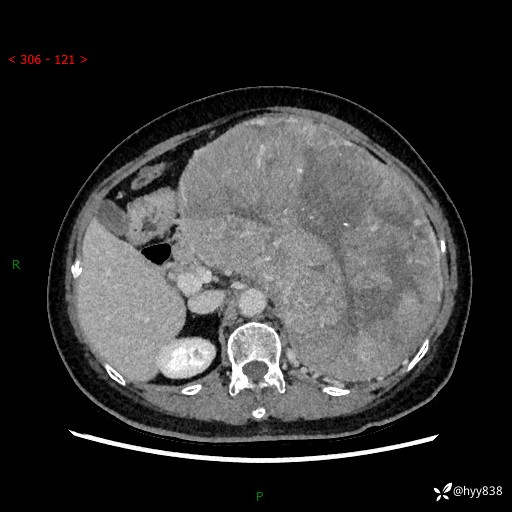

据说只有腹膜后,才能见到如此巨大的肿块---(有结果)

主诉:发现腹膜后占位1周

简要病史:患者1周前因头晕在当地第二人民医院检查发现左侧腹膜后区巨大富血供占位性病变,患者自诉腹部稍硬,无其他不适,无血尿,无腰痛等不适,患者为求进一步治疗来我院,门诊以“腹膜后占位性病变”收入我科。 起病以来,患者精神、饮食、睡眠可,大便正常,小便如上述,体力体重无明显改变。

临床诊断:腹膜后占位

腹部CT增强(动脉期+静脉期 ) ---平扫外院